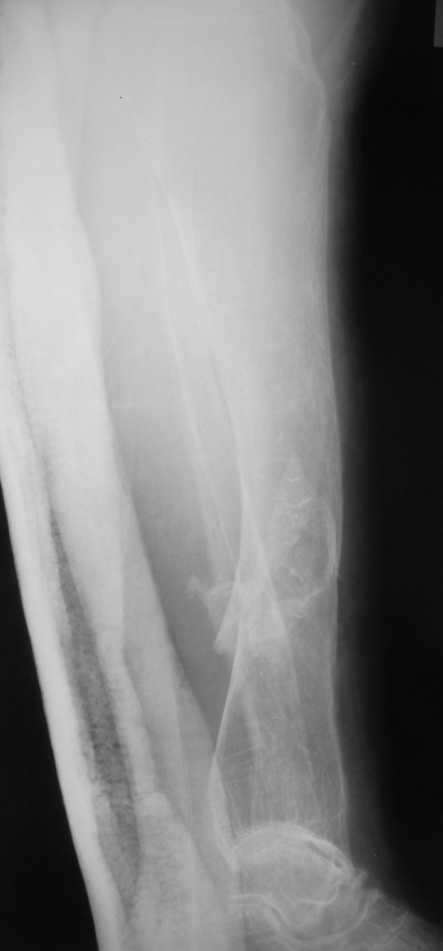

Но даже при малоинвазивной методике лечения применимой для даной больной существуют следующие проблемы: выраженный остеопороз, тонкий кортикал, очень широкий канал.

Контрольные рентгенограммы прилагаю.

Проблема в том, что в сагитальной плоскости угол голеней =30 градусам. Ширина канала 30.

Если при введении стержня будет видно, что из-за искривления дело идет к перфорации стенки, надо будет сделать чрескожную остеотомию на уровне кончика стержня.